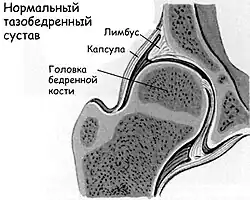

Тазобедренный сустав новорождённого даже в норме является незрелой биомеханической структурой. Его суставная впадина уплощена, она расположена более вертикально, в сравнении с «взрослым суставом», связки сустава избыточно эластичные. Бедренная головка удерживается в суставной впадине за счёт напряжения суставной капсулы, собственной связки (круглой связки тазобедренного сустава). Смещению бедренной кости вверх препятствует хрящевая пластинка вертлужной впадины, которая называется «лимбус» (вертлужная губа – labrum – [лат.] «губа, край»).

При нарушении развития сустава (дисплазии) мы видим (см. рисунок) более плоскую и скошенную суставную впадину; избыточно эластичные связки и суставная капсула не способны удерживать головку бедренной кости в суставной впадине, она смещается вверх и латерально (кнаружи). При этом лимбус выворачивается (смещается вверх) и деформируется, он теряет способность удерживать смещение головки бедренной кости. При определённых движениях головка бедра может выйти за пределы вертлужной впадины. Такое состояние сустава называется «подвывих»[5].

При тяжёлой форме дисплазии тазобедренного сустава головка бедренной кости полностью выходит за пределы вертлужной впадины. Такое состояние называется «вывих бедра». Головка бедра располагается выше суставной впадины, лимбус вворачивается внутрь сустава и находится ниже головки бедра, суставная впадина заполняется жировой и соединительной тканями. Это существенно затрудняет вправление вывиха[5].